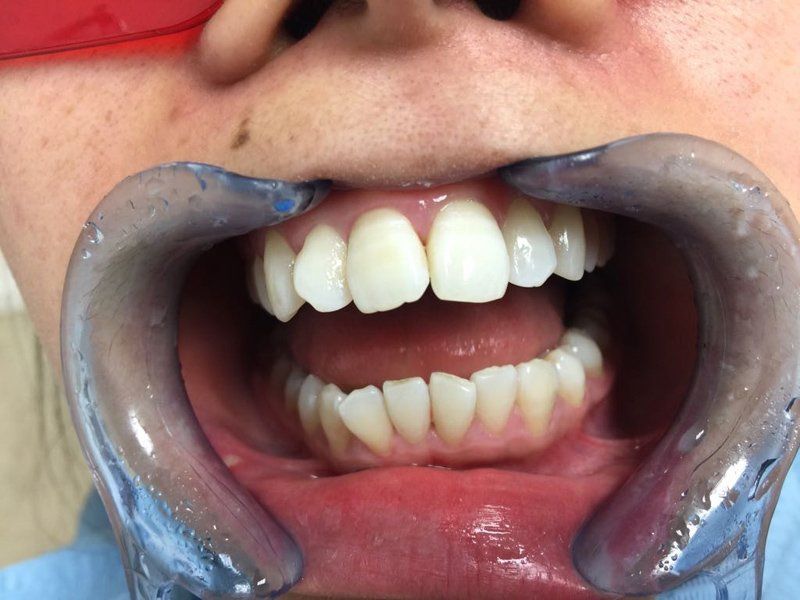

Sbiancamento con led

Prima e dopo una sola seduta d’igiene orale professionale in paziente maschile fumatore, il risultato può essere ulteriormente migliorato con un trattamento di sbiancamento.